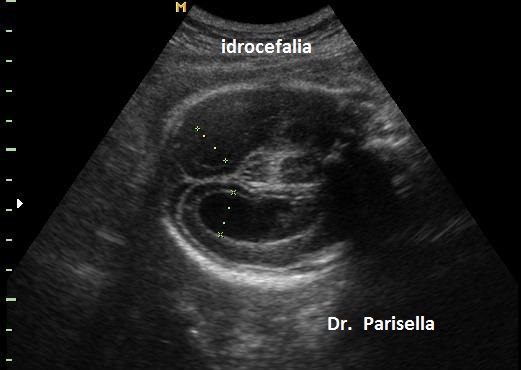

Possono essere presenti: 6) piede torto; 7) idrocefalia.

I primi tre segni (segno del limone, obliterazione della cisterna magna, cervelletto a banana), c.d. segni indiretti, hanno una elevata sensibilità nella diagnosi dei difetti aperti e sono espressione della sindrome di Chiari tipo 2. Questa è la conseguenza della perdita di liquido cefalo-rachidiano attraverso il difetto spinale; la diminuzione della pressione idrostatica provoca iposviluppo della fossa cranica posteriore con conseguente erniazione del tronco encefalico e del cervelletto che si piega assumendo il classico aspetto a banana. La perdita di liquido cerebrospinale attraverso il difetto spinale provoca un aumento dei livelli di alfa-fetoproteina nel liquido amniotico e nel siero materno.